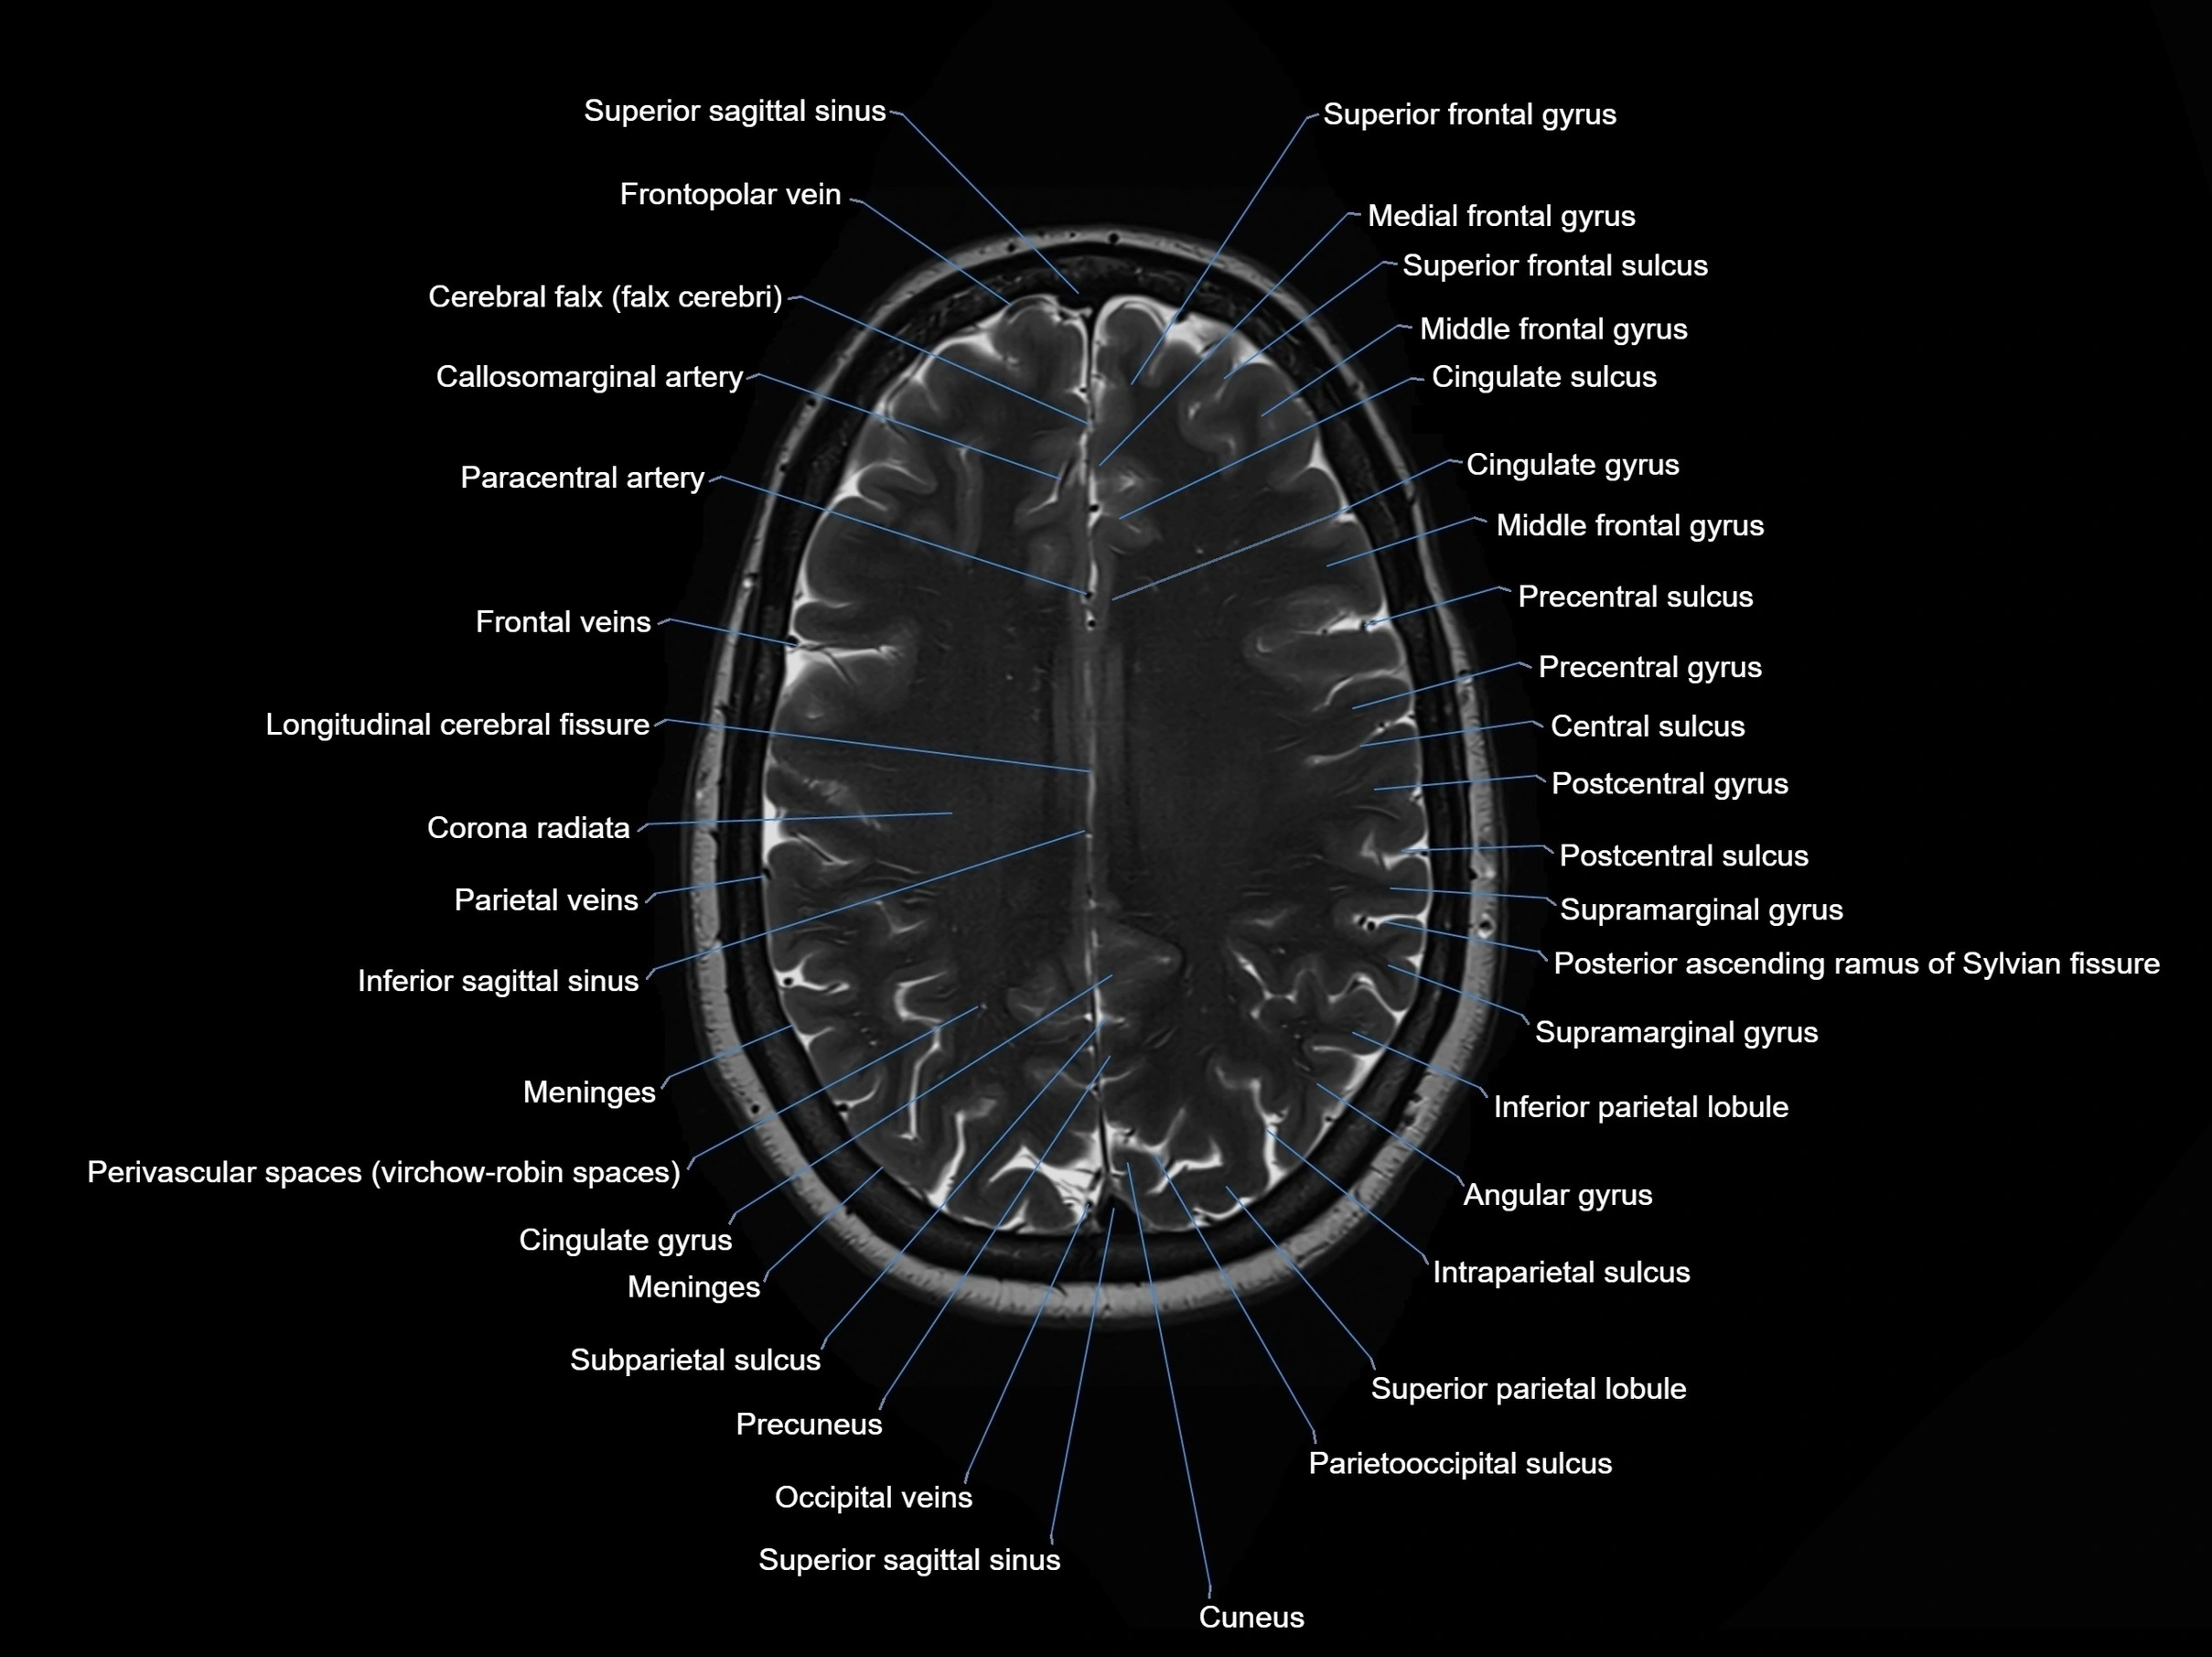

MRI images